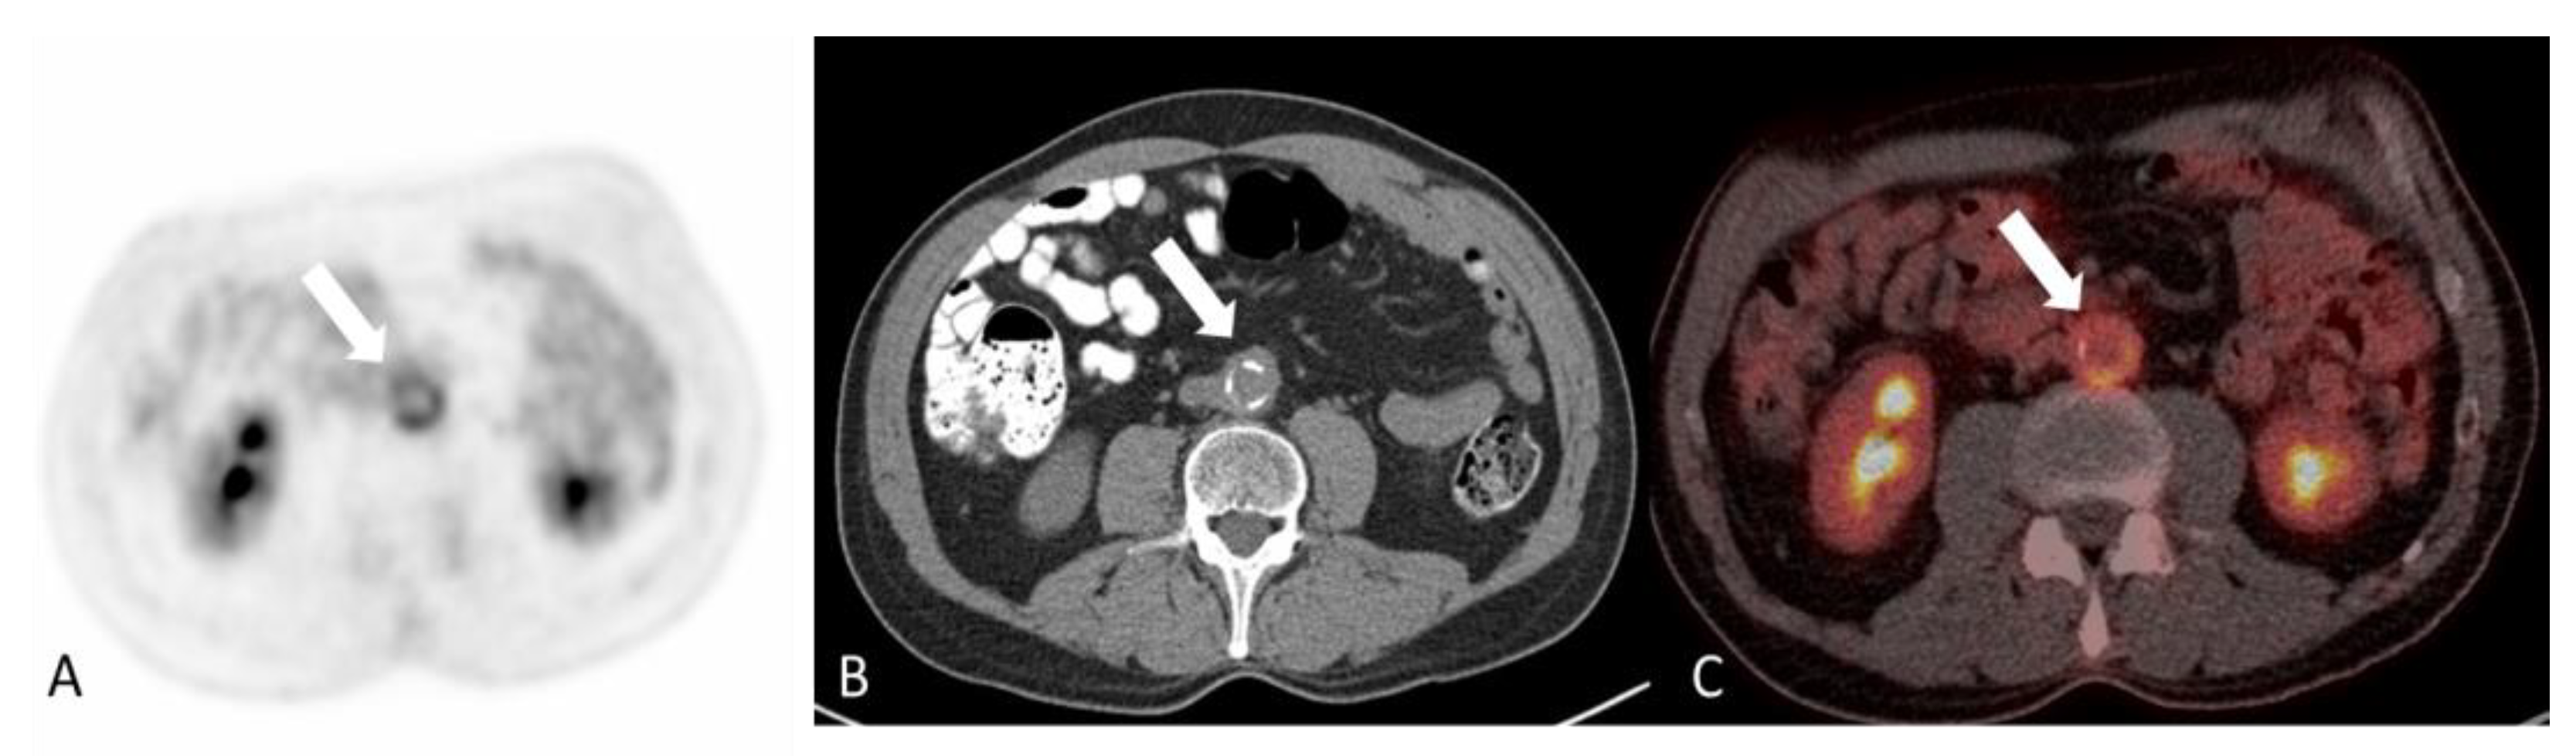

2.2.1. Polyarteritis Nodosa

- Singhal, M.; Gupta, P.; Sharma, A.; Lal, A.; Rathi, M.; Khandelwal, N. Role of multidetector abdominal CT in the evaluation of abnormalities in polyarteritis nodosa. Clin. Radiol. 2016, 71, 222–227. [Google Scholar] [CrossRef] [PubMed]

- Chen, Z.; Zhao, Y.; Wang, Q.; Li, Y.; Li, H.; Zhou, Y. Imaging features of 18F-FDG PET/CT in different types of systemic vasculitis. Clin. Rheumatol. 2022, 41, 1499–1509. [Google Scholar] [CrossRef] [PubMed]